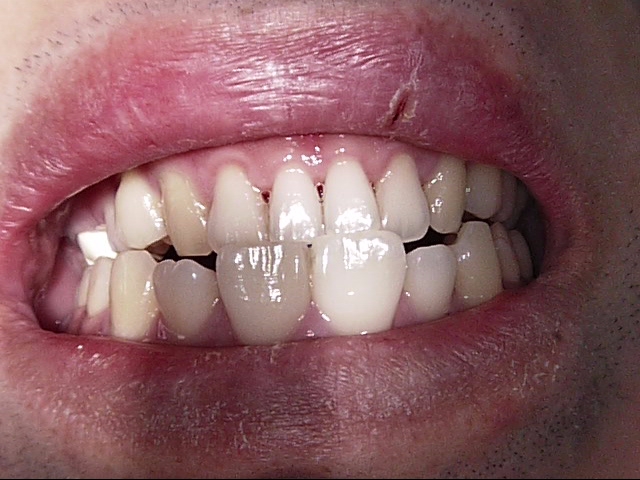

白い歯のなかでも保険適応のPEEK冠といって、割れにくい被せ物もあるのですが、色が真っ白になってしまうので、悪目立ちします。

PEEK冠の1例↓